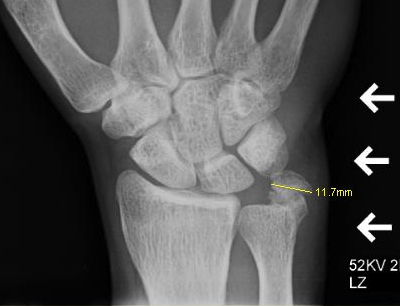

X-ray

May show calcific deposits within the tendon sheath